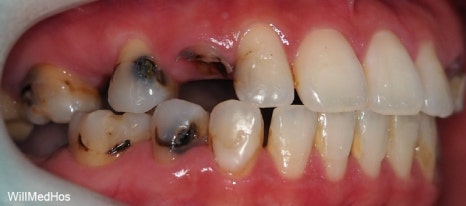

먼저 구강 사진 부터 보도록 하겠습니다.

이미 충치들과 염증으로 인해 치관을 다 없어지고 잔존 뿌리들만 겨우 남아있는 상태들의 치아들

염증으로 인하여 살리기 힘든 치아들도 다수 있었습니다

나이가 젊으신 분인만큼 최대한 살릴 수 있는 치아들은 살리고 임플란트 필요 치아들을 치료하는 방향으로 계획을 잡았습니다.